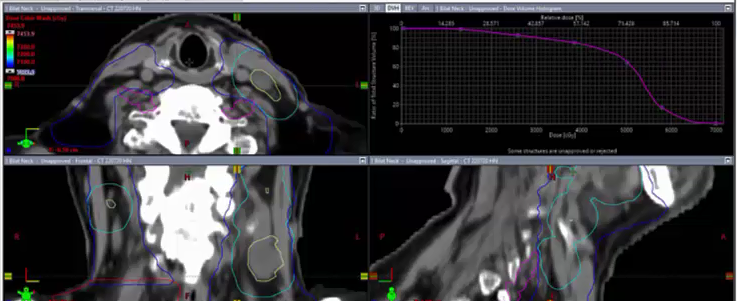

10/31/2022 - Dr. David Sher - Radiation Oncology - US Head & Neck

keep esophagus off 2 cm, 4-5 field VMAT, push a lot harder, omit level 6, PTV, 15 Gy, bilateral tongue, node positive, post-op tonsil, 60 Gy margins, negative margins, chemoradiation, ipsilateral neck, cisplatin, T2N2, tonsillectomy, left neck dissection, SCC, CTV, uvula, soft palate